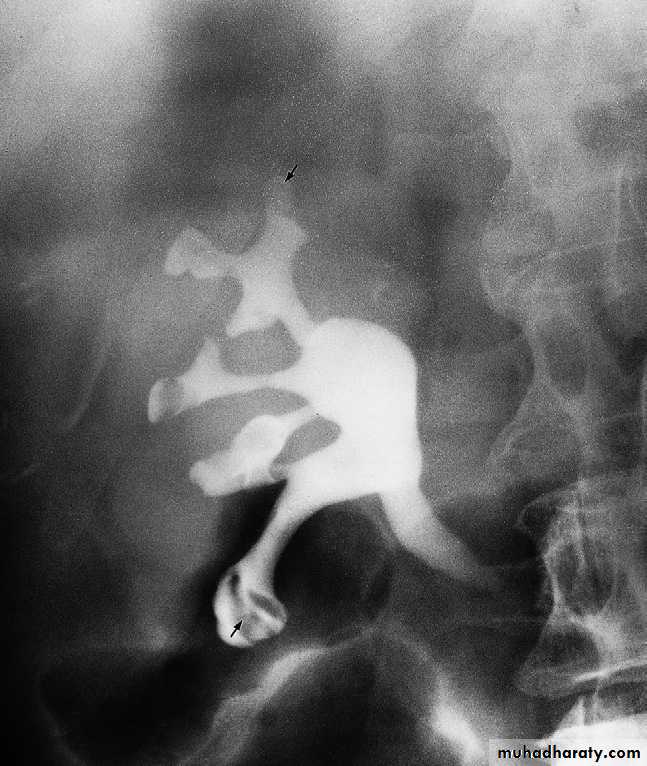

mainly replaced by CT scan & CT urography in patients with suspected acute obstruction, which is usually caused by a calculus.-In Plain films may demonstrate the calculus responsible for the obstruction .

-Following injection of intravenous contrast medium, a film of the renal tract is taken at approximately 15 minutes. If the urogram is normal, with contrast seen in normal, undistended ureters bilaterally,then this effectively rules out ureteric colic as the cause of acute pain.

-If one of the ureters is obstructed, then adense nephrogram will be seen and opacification of the pelvicaliceal system and ureter on the obstructed side takes much longer. Delayed films are, therefore, essential part of any IVU.